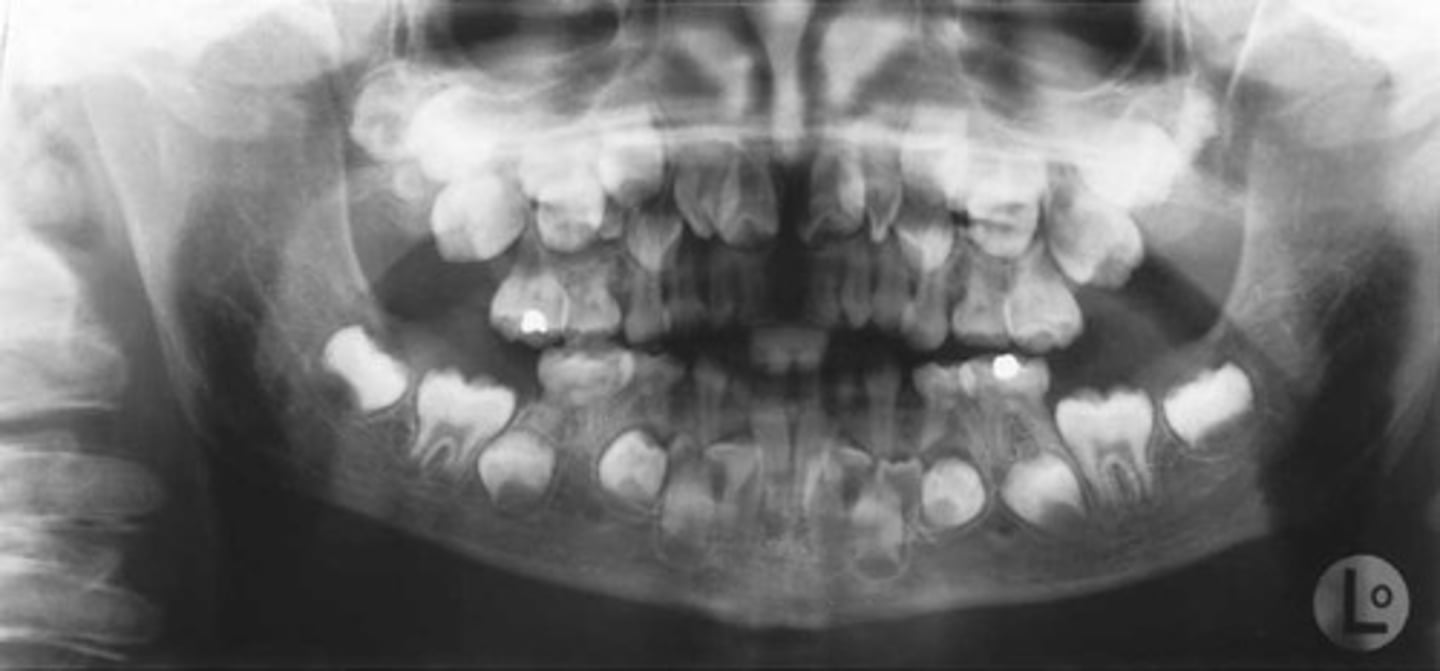

Oral features of Cleidocranial dysplasia

-High palate

-delayed/failed eruption

-Many teeth

-paranasal sinuses missing

Cleidocranial dysplasia (oral photo)